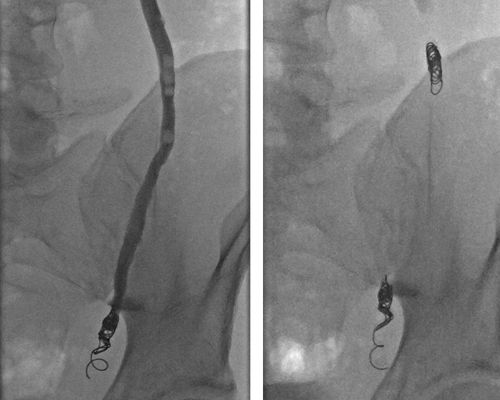

Varicocele embolization is performed through a small puncture in the neck or groin. Under real-time imaging guidance, a thin catheter is navigated to the abnormal veins draining the testicle. Embolic materials are then delivered to block these veins, redirecting blood flow through normal pathways.